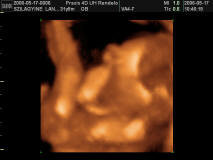

Nemrég még én is nyavalyogtam, hogy milyen lassan telik a terhesség eleje, oszt ma vagyunk 20+1 idősek, szóval beindult